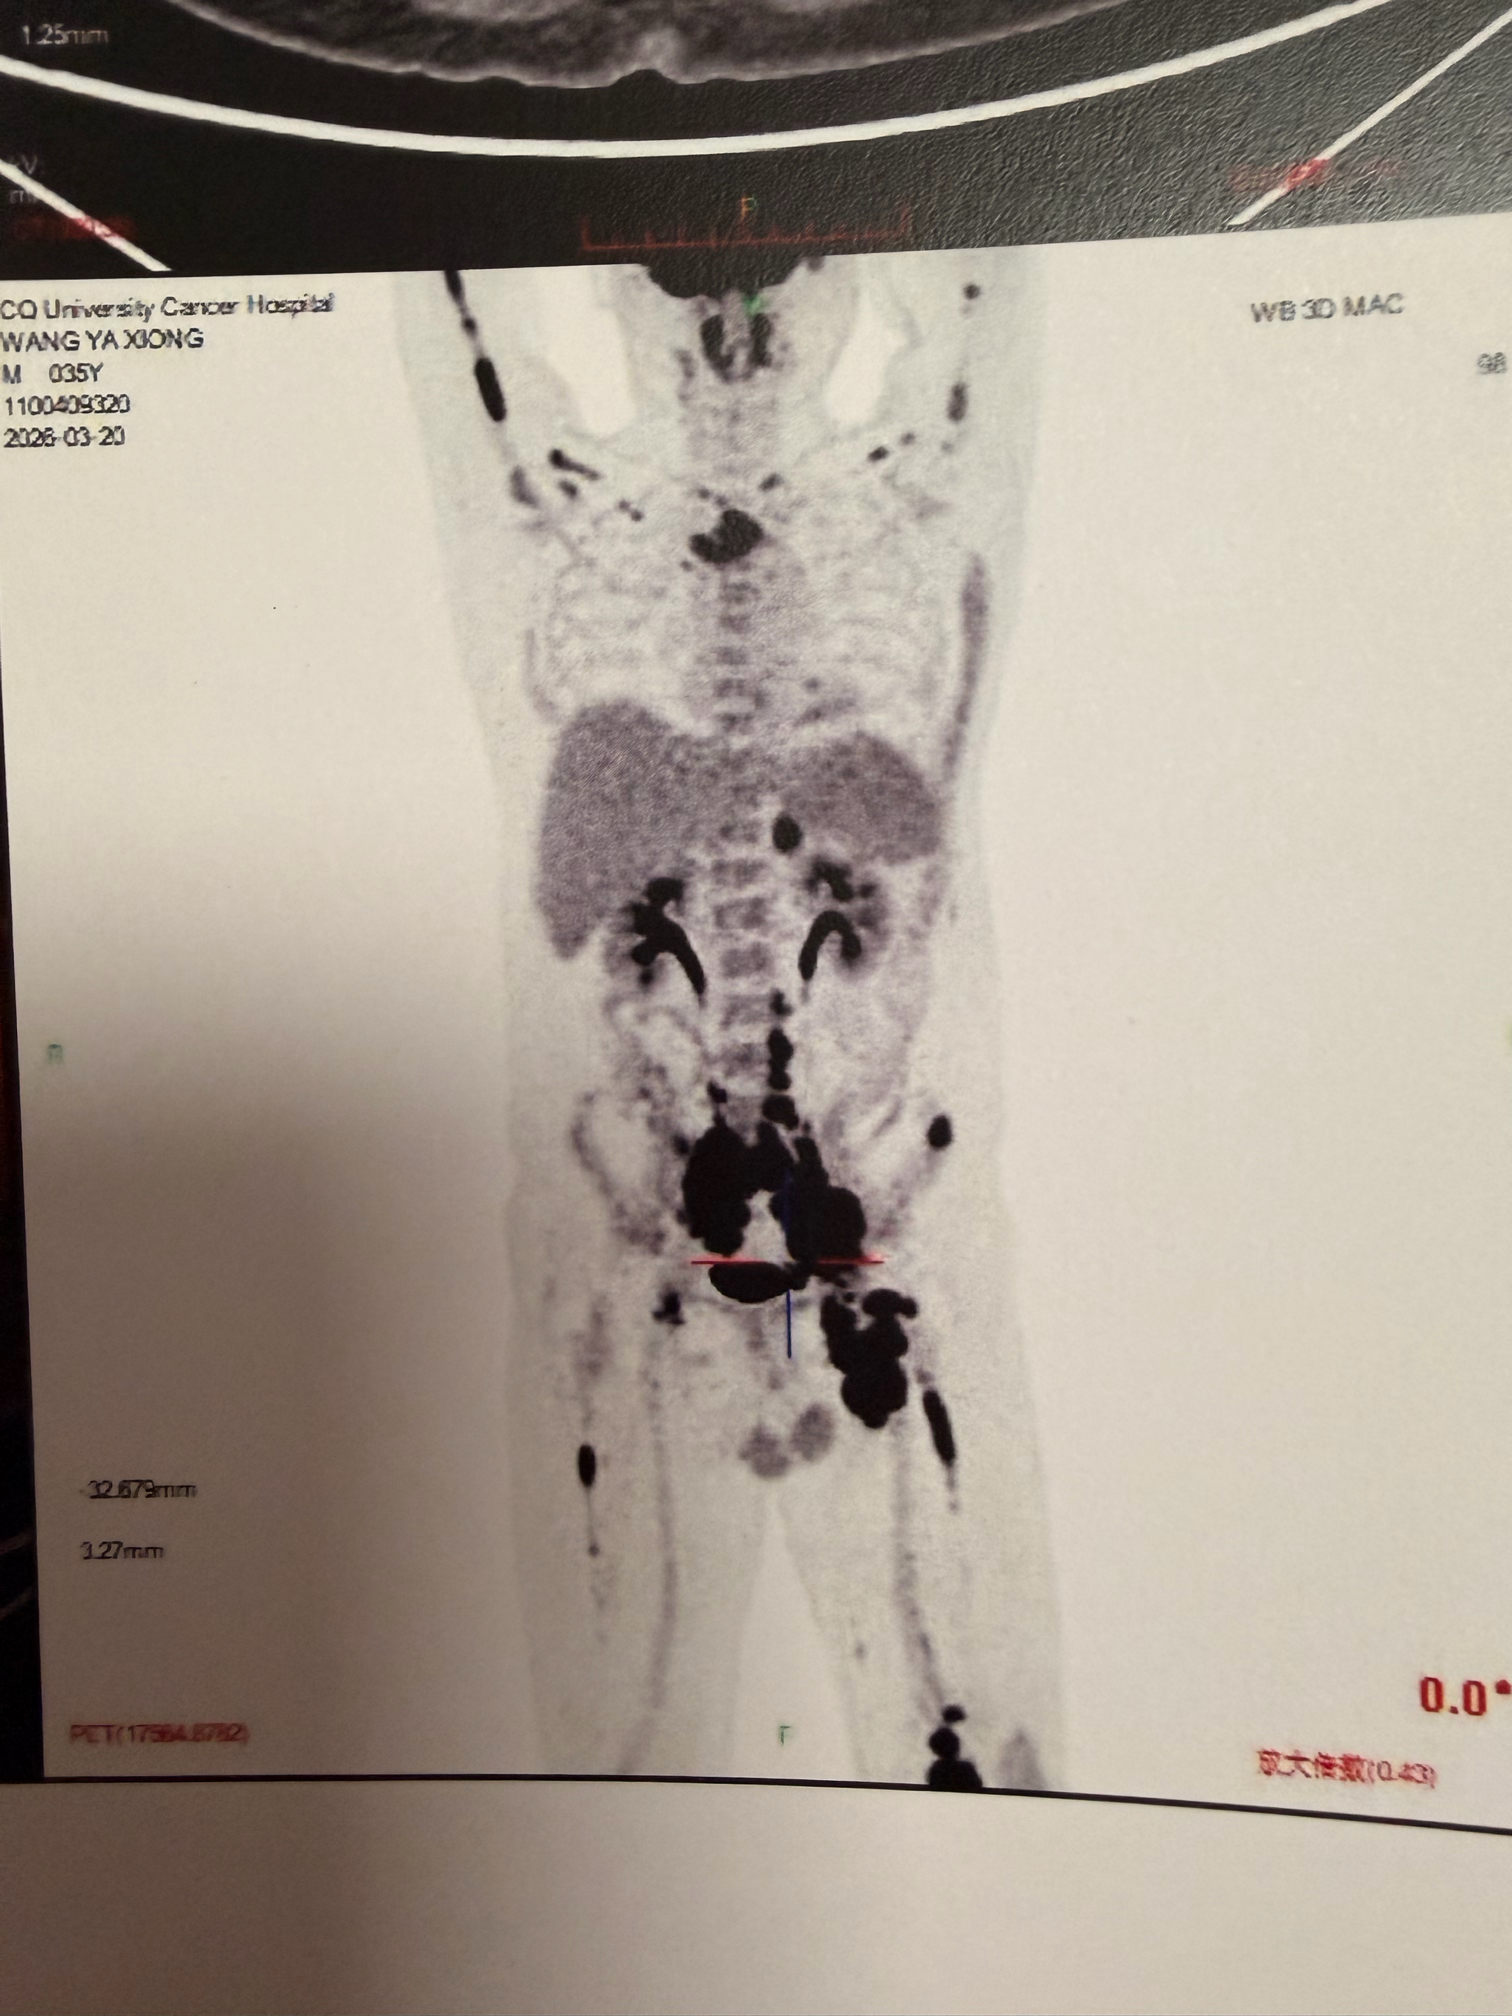

弥漫大B,IV期,骨髓侵犯,GCB型,伴CD5+,myd88和CD79b变异

petCT显示很多地方都累及

骨穿报告显示累及骨髓